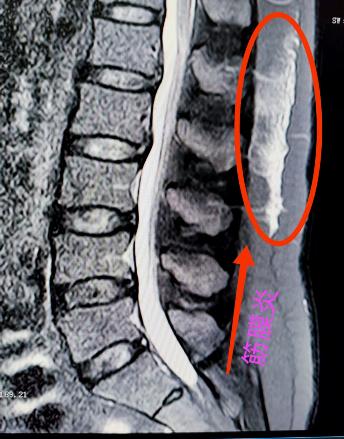

腰椎小關節(jié)增生紊亂:腰椎后方兩側成對的小關節(jié),負責穩(wěn)定脊柱并引導活動。它們如同門上的合頁,一旦因勞損、退變導致軟骨磨損、骨質增生,或發(fā)生微小錯位,就會引發(fā)深層、定位模糊的腰痛。疼痛常在腰部扭轉、后伸時加劇,有時晨起僵硬感明顯。